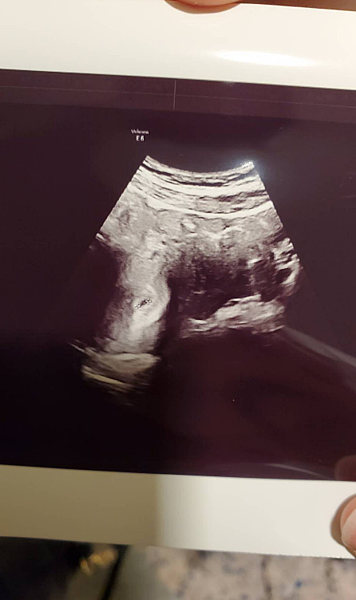

▌第三次產檢(9周) 被子宮裡的血塊嚇到趕緊安胎 ▌

第三次產檢前 其實我們全家都很興奮

還一職討論有沒可能透過超音波猜到是弟弟還妹妹

因為小雞毛差不多也是這時期就有照到一個小亮點

醫生就已經判定是男生的機會很高

沒想到才進去剛躺下來

醫生才拿起超音波 就跟我們說子宮有照到血塊![]()

這下我真的整個腦袋嚇傻了 很擔心影響小寶寶的成長

但醫生說 只要沒有繼續出血 尤其是鮮血

那可能是早期我有出血留下的

只要血塊沒有變大影響寶寶生長 那以後血塊會慢慢被身體吸收

這段時間還是一樣 多休息 不要太累 最好躺床

我就乖乖地立刻跟公司請了安胎假

回家後回看了N次超音波錄影的回看

他小小的手跟腳 動來動去

似乎再跟我們打招呼

還是覺得真的是一種好神奇的感覺